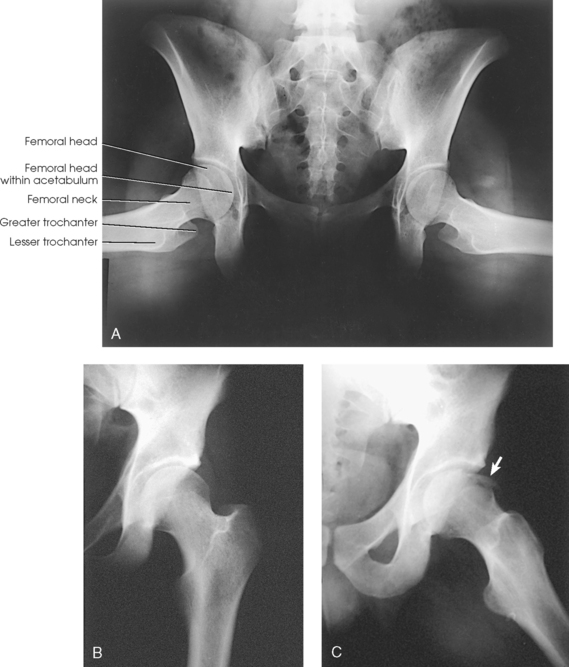

The femur is the longest, strongest, and heaviest bone in the body. The proximal end of the femur consists of a head, a neck, and two large processes: the greater and lesser trochanters (Fig. 7-4). The smooth, rounded head is connected to the femoral body by a pyramid-shaped neck and is received into the acetabular cavity of the hip bone. A small depression at the center of the head, the fovea capitis, attaches to the ligamentum capitis femoris (Fig. 7-5; see Fig. 7-4). The neck is constricted near the head but expands to a broad base at the body of the bone. The neck projects medially, superiorly, and anteriorly from the body. The trochanters are situated at the junction of the body and the base of the neck. The greater trochanter is at the superolateral part of the femoral body, and the lesser trochanter is at the posteromedial part. The prominent ridge extending between the trochanters at the base of the neck on the posterior surface of the body is called the intertrochanteric crest. The less prominent ridge connecting the trochanters anteriorly is called the intertrochanteric line. The femoral neck and the intertrochanteric crest are two common sites of fractures in elderly adults. The superior portion of the greater trochanter projects above the neck and curves slightly posteriorly and medially.

Fig. 7-4 Proximal right femur. A, Anterior aspect. B, Medial aspect. The body is positioned 15 to 20 degrees posterior from head. C, Posterior aspect. D, Posterior aspect of right proximal human femur. Note anatomic details and compare with C.

The angulation of the neck of the femur varies considerably with age, sex, and stature. In the average adult, the neck projects anteriorly from the body at an angle of approximately 15 to 20 degrees and superiorly at an angle of approximately 120 to 130 degrees to the long axis of the femoral body (Fig. 7-6). The longitudinal plane of the femur is angled about 10 degrees from vertical. In children, the latter angle is wider—that is, the neck is more vertical in position. In wide pelves, the angle is narrower, placing the neck in a more horizontal position.